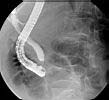

Endoscopische Retrograde Cholangio- Pancreaticografie (E.R.C.P.)

E.R.C.P.

Een specifiek onderzoek voor de pancreas en de galwegen. Het gebeurt in samen werking met een internist die de endoscopie verricht. De endoscoop wordt ingebracht via de mond tot ter hoogte van de uitmonding van de galwegen in de dundarm( t.h.v. de papil van Vater) Daar wordt dan via een dunne katheter contrast ingebracht in de galwegen. Zo kan men eventueel aanwezige galstenen visualiseren. Ook kan er tijdens het onderzoek overgegaan worden tot het verwijderen van de galstenen.

Voorbereiding :

De patiënt is nuchter sinds ten minste vier uur voor het onderzoek

Best wordt hij/zij met een bed naar de dienst radiologie gebracht

Een waakinfuus wordt aangelgd, om eventuele probelemn tijdens het onderzoek te kunnen opvangen, en om pijnmedicatie en verdoving toe te dienen

Voorbereidende foto van de leverstreek wordt genomen voor het onderzoek

Nazorg:

Aandacht voor het coorect wakker worden van de patiënt

Infuus zolang de patiënt onvoldonde zelf kan drinken

Pijnmedicatie zo ndig